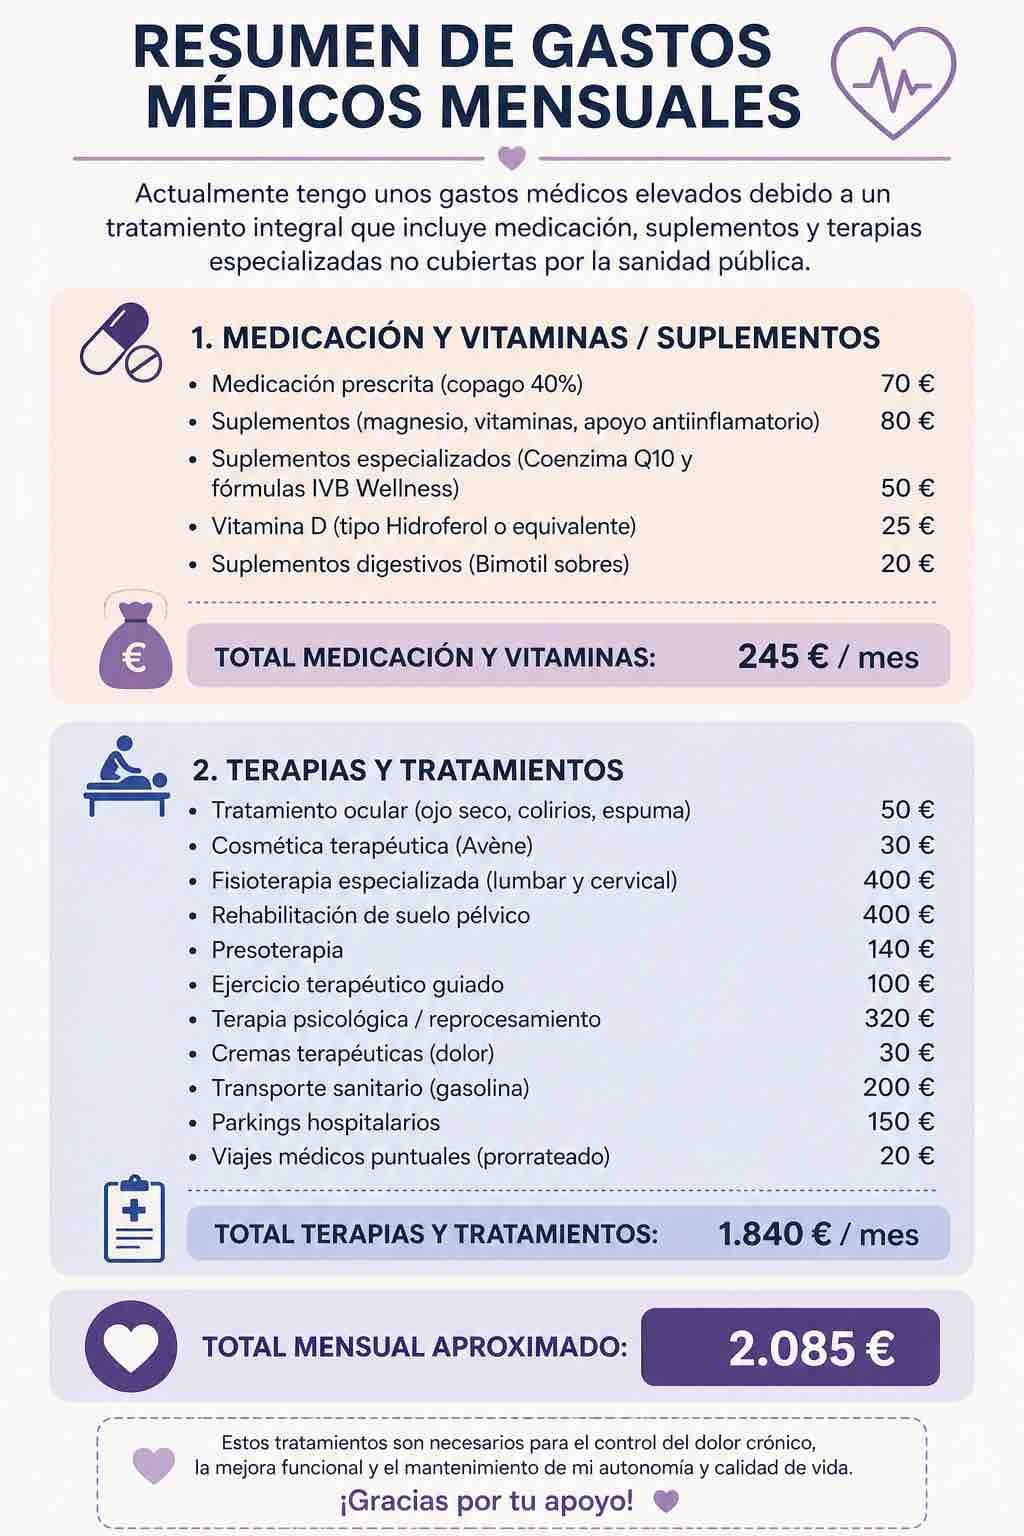

Hoy, pido tu ayuda. Mi objetivo es poder costear los tratamientos que necesito desesperadamente para estabilizarme y mejorar mi calidad de vida. Tu donación se destinará directamente a:

• Rehabilitación de Suelo Pélvico y Electroestimulación: Terapias esenciales para reducir mi dolor neuro-pélvico.

• Citas Médicas Especializadas y Pruebas: Para seguir buscando soluciones y un manejo integral de mi caso.

• Medicación y Desplazamientos: Para afrontar el alto coste de mi tratamiento diario.

Today, I ask for your help. My goal is to afford the treatments I desperately need to stabilize and improve my quality of life. Your donation will go directly towards:

• Pelvic Floor Rehabilitation and Electrostimulation: Essential therapies to reduce my neuro-pelvic pain.

• Specialized Medical Appointments and Tests: To keep searching for solutions and a comprehensive management of my case.

• Medication and Travel Expenses: To manage the high cost of my daily treatment.